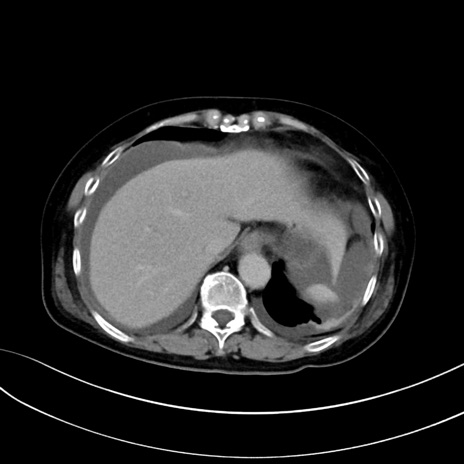

症例13 CT(横断像)1日半後